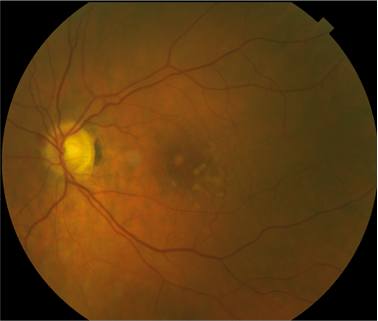

FUNDUS DESCRIPTION: |

OD OS |

OD Red-Free: Pre-Injection: Arterial: A-V: Venous: Recirculation: Late:

OS Red-Free: Venous: Recirc: Late:

Impression